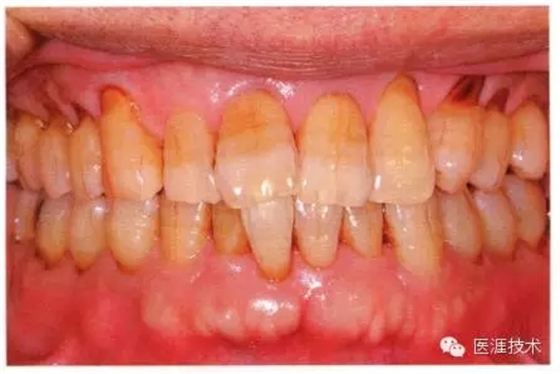

健康牙周組織的牙齦邊緣呈珊瑚粉,邊緣牙齦略呈圓弧狀。牙間可見三角形的牙間乳頭,牙齦邊緣相連呈貝殼形。

附著齦與游離齦相連時(shí),有時(shí)有游離齦溝存在(成人的30~40%)。

附著齦通過膠原纖維牢固結(jié)合骨骼與牙骨質(zhì),因此可見不可動(dòng)、硬而緊繃的點(diǎn)彩(橘皮樣點(diǎn)狀凹凸)。

從牙齦牙槽粘膜到根尖有牙槽粘膜。牙槽粘膜為暗紅色,與骨骼結(jié)合較松,故可動(dòng)。

健康且正常的牙周組織臨床圖像